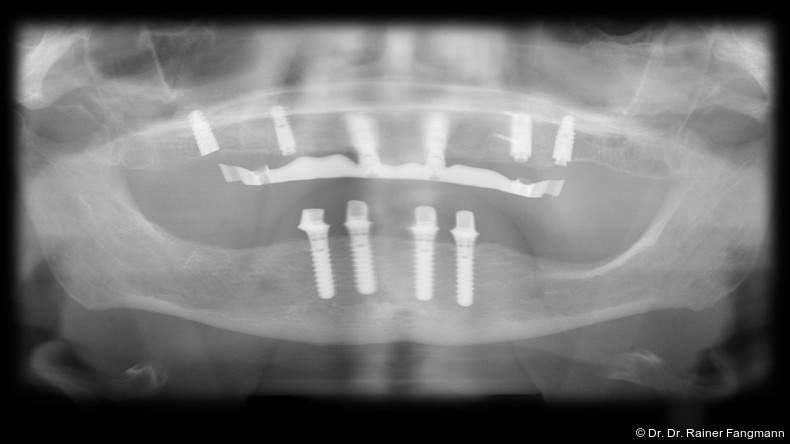

Prothetischer Behandlungsablauf

Wenn die geraden und/oder angulierten Basisaufbauten (Ankylos® Balance C/schmal) in situ sind, werden diese mit den Schutzkappen für Balance Basisaufbau schmal für die Zeit zum Schutz versorgt. In dieser Situation erfolgt entweder eine Situationsabformung oder ein Situationsscan. Im zahntechnischen Labor wird aufgrund dieser Basis ein Pattern-Resin-Steg hergestellt, der die Retentionskappe für Balance Basisaufbau schmal einbindet. Dieser Steg wird der Zahnarztpraxis getrennt angeliefert. Die Retentionskappen werden in situ eingebracht und mit der Halteschraube okklusal M 1,6 mm Hex extralang fixiert. Der getrennte Pattern- Resin-Steg wird intraoral mit dem gleichen Material verblockt. Danach erfolgte die typische Implantatabformung auf Abutmentniveau mit z. B. Dentsply Sirona Aquasil Ultra+ über einen laborgefertigten individuellen Abformlöffel. Im zahntechnischen Labor wird dann das klassische Meistermodell mit dem Basisaufbau entsprechend der Implantatanzahl hergestellt. Dieses wird samt der Unterkieferwachsaufstellung und dem Gegenkiefer, der auch 3D-gedruckt sein kann, und einer Bißnahme versandt. Der Auftrag wird vom Zahntechniker in der ATLANTIS-WebOrder parallel eingegeben. Die Suprastruktur wird erst nach einer Überprüfung und der endgültigen Freigabe des Designs im ATLANTIS ISUS-Viewer gefertigt. Die Implantat-Suprastruktur wird an das Dentallabor geliefert, das daraus die fertige Prothetiklösung herstellt und diese dem Zahnarzt schickt.

Fertigungstechniken für Stege